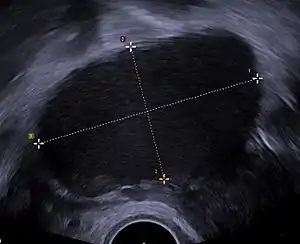

Transvaginal ultrasonography of a hemorrhagic ovarian cyst, probably originating from a corpus luteum cyst. The coagulating blood gives the content a cobweb-like appearance.